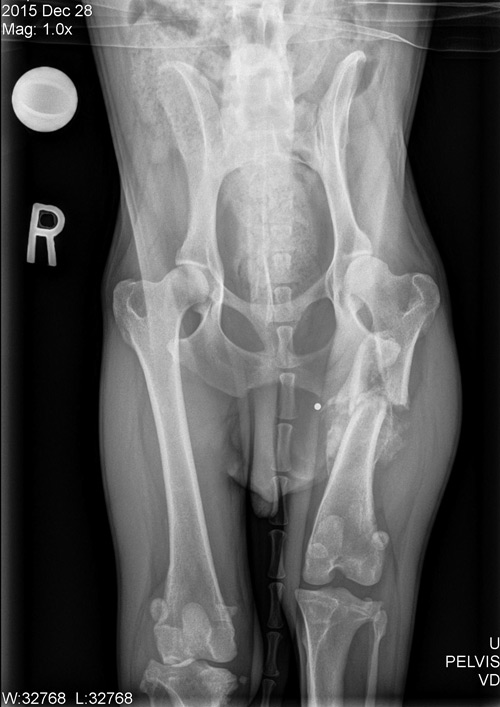

Six weeks after his back surgery, Scruffy was recovered enough to address the rest of his orthopedic problems. Arthroscopy was performed on both of his knees to remove damaged meniscal tissue and evaluate the damage in the CCL’s. Arthroscopy involves looking into a joint with a camera to evaluate the interior surfaces. It is less invasive than traditional ways of looking into a joint, and recovery time is shorter. A tibial plateau leveling osteotomy (TPLO) was performed on the left side, due to the steep tibial slope (33°). A TPLO diminishes the slope angle and stabilizes the knee. The right tibial plateau had a flatter tibial plateau slope due to the way the tibia healed from the previous break.

FasTak stabilization was performed on the right knee to stop cranial drawer. With this technique a strong line is secured between the femur and tibia using an absorbent screw. This technique works best in smaller breed dogs and when the tibial slope is relatively low. Scruffy went home the next day and his foster Mom worked hard to re-train his muscle and keep his exuberance controlled so that both of his knees could heal.